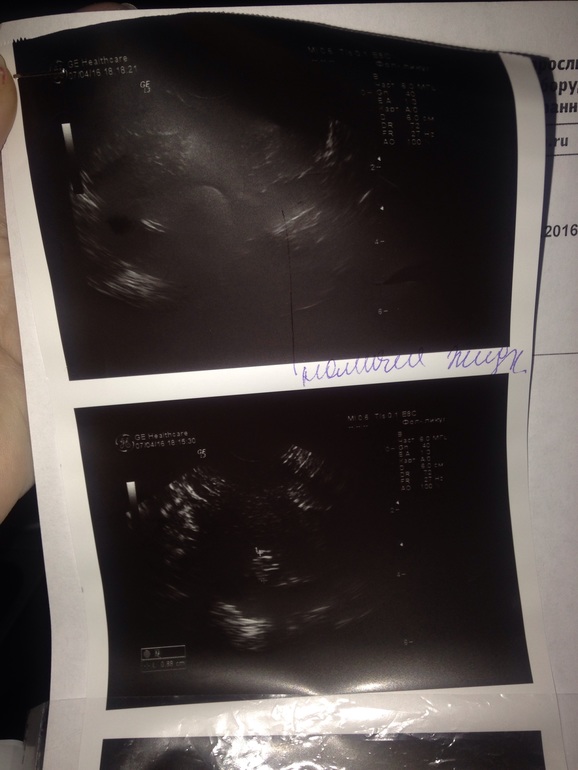

Прикладываю фото

ГСГ, ЭХО, МСГ, ФертилоскопияПодскажите пож.. Прошла эхогсг, слава Богу труба проходима, но диск с видео мне не записывали, и точное время(через сколько минут-секунд), когда раствор побежал по трубе-тоже не говорили. Но врач сразу сказала, что водичка побежала побежала, все проходимо.. Но по фото вообще не видно трубы ... Что-то меня это настораживает ((( при снимке узи картины , должна полностью визуализироваться труба или только при гсг снимке она видна ?